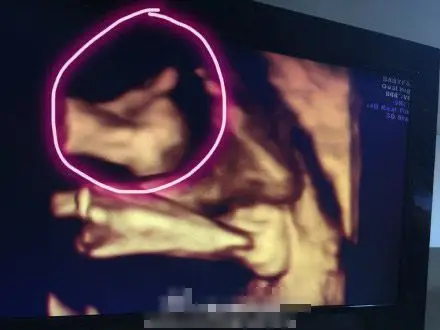

林志颖晒双胞胎儿子b超照 弟弟孕肚中比赞